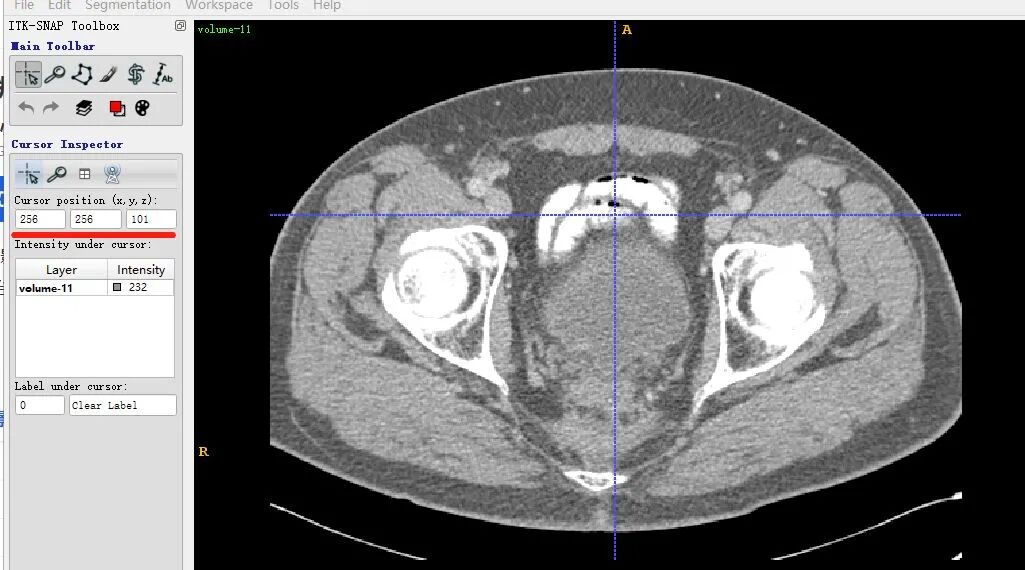

volume-11.nii (466, 512, 512) 232.0

表明该数据shape为(466,512,512),注意对应的顺序是z,x,y。z其实是slice的索引。x和y是某一个slice的宽和高。

同一个slice在ITK-SNAP可视化结果(注意这里(x,y,z=(256,256,101)),因为itk-snap默认从1开始索引):

可以发现,上下两张x轴一样但y轴方向上下翻转了,这是由于matplotlib显示方式不同,但是不会出现读取数据对不齐的问题。